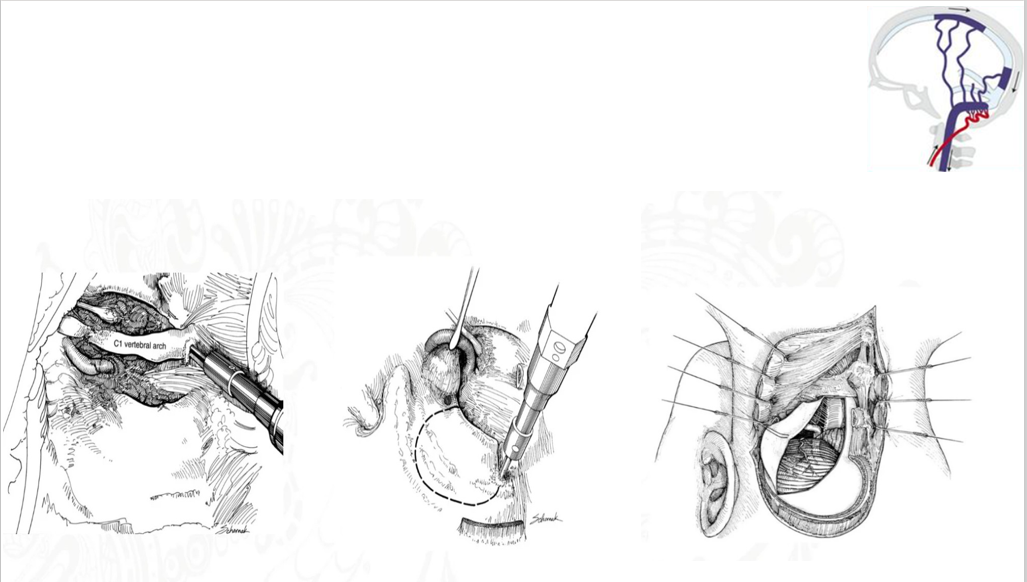

经过神经外科医师团队讨论,根据患者病情,畸形血管瘘口迂曲细小,介入栓塞导管估计难以置入,或者术中发生破裂出血、脑干梗塞的风险极高,综合判断,开颅手术夹闭瘘口才是最适合黄先生的治疗方案。采用术式:复合手术室下行开颅颅颈交界区硬脑膜动静脉瘘夹闭术。步骤:左侧桡动脉穿刺留置5F造影管至左椎动脉、俯卧位、左侧枕部旁正中 。

手术中

手术入路示意图

经过神经外科李学东主任手术团队的努力,手术顺利实施,团队成员有条不紊进行左侧桡动脉置管至左椎动脉、俯卧位碳纤维头架固定、特殊体位消毒、左侧枕部旁正中入路等一系列操作,通过术中标记造影,滑轨CT定位,在脑干及周围神经血管的周围,循异常迂曲扩张的引流静脉找到瘘口,予以夹闭烧灼,术中DSA证实畸形血管已消失、滑轨CT证实无颅内出血等异常。